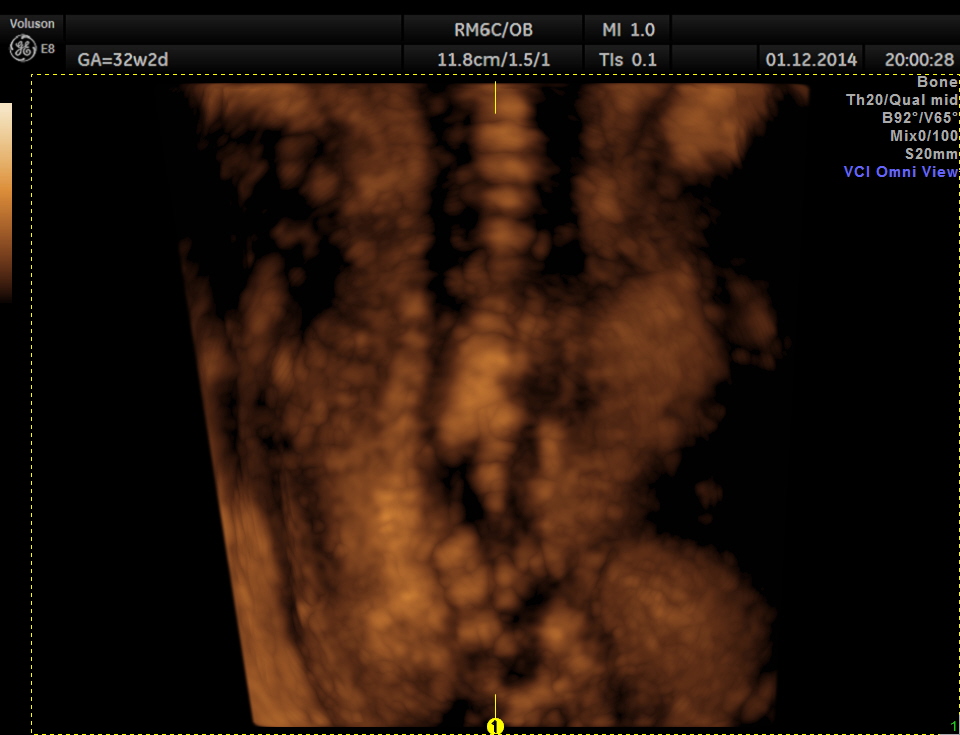

3D view of the same.

Careful examination revealed a neural tube defect with meningo myelocele at the lumbo sacral level.

Spinal deformity was also noted.